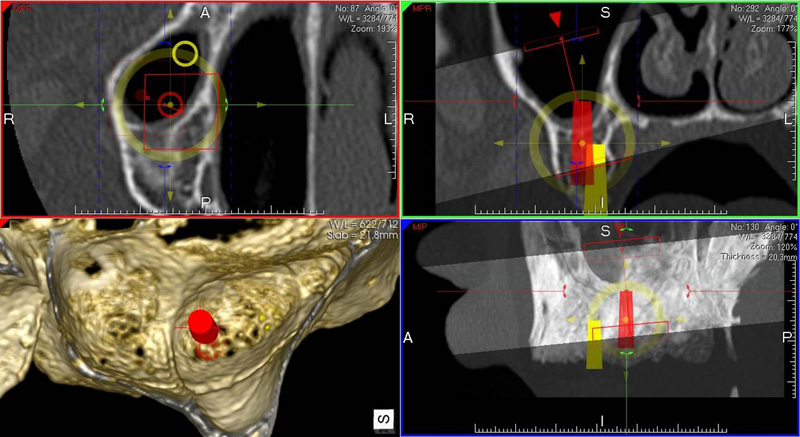

NewTom Implant Planing

Jedná se o plánovací program, který využívá dat získaných při vyšetření pomocí přístroje New Tom. Tento program umožňuje tříprostorovou počítačovou simulaci při plánování pozic implantátů.

Součástí programu je i databáze, ve které mohou být uloženy všechny typy implantátů od všech výrobců, včetně jejich délek, průměrů i tvarů.

Lékař si vytvoří všechny typy zobrazení potřebných pro naplánování – tedy 2D snímky (panoramatický), příčné řezy i 3D model.

Vidí zde i důležité anatomické útvary – čelistní dutinu, průběh nervu atd. Po proměření množství kosti – šířky i výšky vybere z databáze vhodný typ implantátu a umístí ho do požadované lokality.

Ihned vidí jeho pozici ve všech 3 rovinách a na všech snímcích i 3D modelu. Může upravovat podle potřeby jeho pozici, sklon atd.

Všechny vybrané a správně umístěné simulované implantáty se ukládají do „počítačové karty“ pacienta s jejich pozicí, délkou, průměrem, typem i sklonem.

Lékař i pacient tedy ještě před vlastní operací vidí, jak by mělo ošetření probíhat a vypadat.